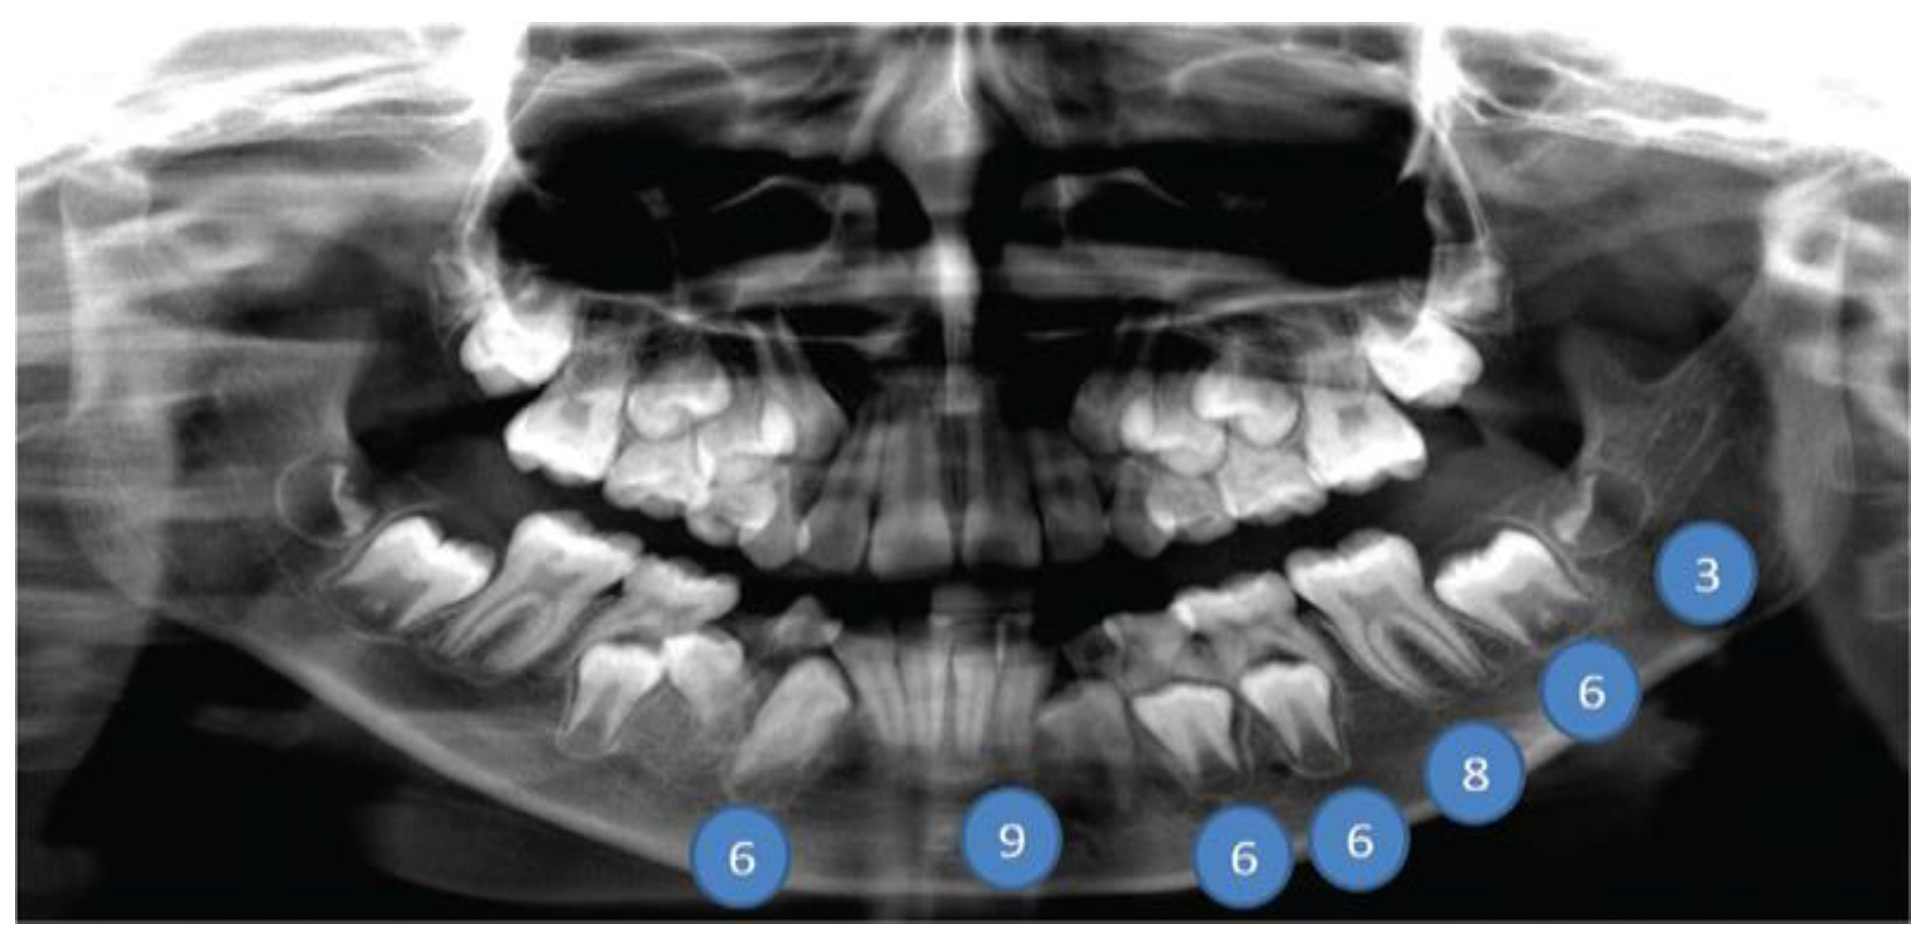

![]() |